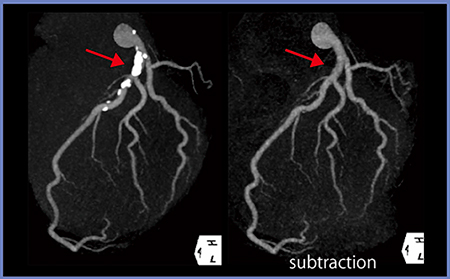

しかし,このサブトラクションCCTAでは,造影画像を撮影する一連のシリーズでマスク画像を撮影する必要があり,1回の息止め時間が長くなる。そこで,当院では,テストインジェクション法を用いて上行大動脈への到達時間を求めて,大動脈が染まらない時相でマスク画像を撮影するプロトコルを作成して検査を行っている。一例を示すと,造影剤注入から7秒後に息止めのアナウンス,11秒後にファーストスキャン,25秒後にセカンドスキャンを撮影する。息止め時間は18秒と短くはないが,サブトラクションCCTAが1回の息止め下で20秒を超えない時間で可能となる(図2)。これによって,左冠動脈はサブトラクションによって石灰化が除去され,内腔が確認できる(図3)。吉岡らの報告では,コンベンショナルなCCTAにサブトラクションCCTAを加えることで,高い診断能が得られることが報告されている3)。

図3 1回の息止め下で撮影された画像からサブトラクション画像を作成